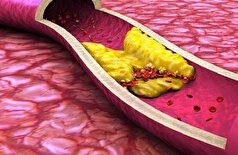

- آلودگی هوا بیسروصدا قلب را تهدید میکند!

- یک دوز از داروی جدید میتواند کلسترول را برای تمام عمر کاهش دهد